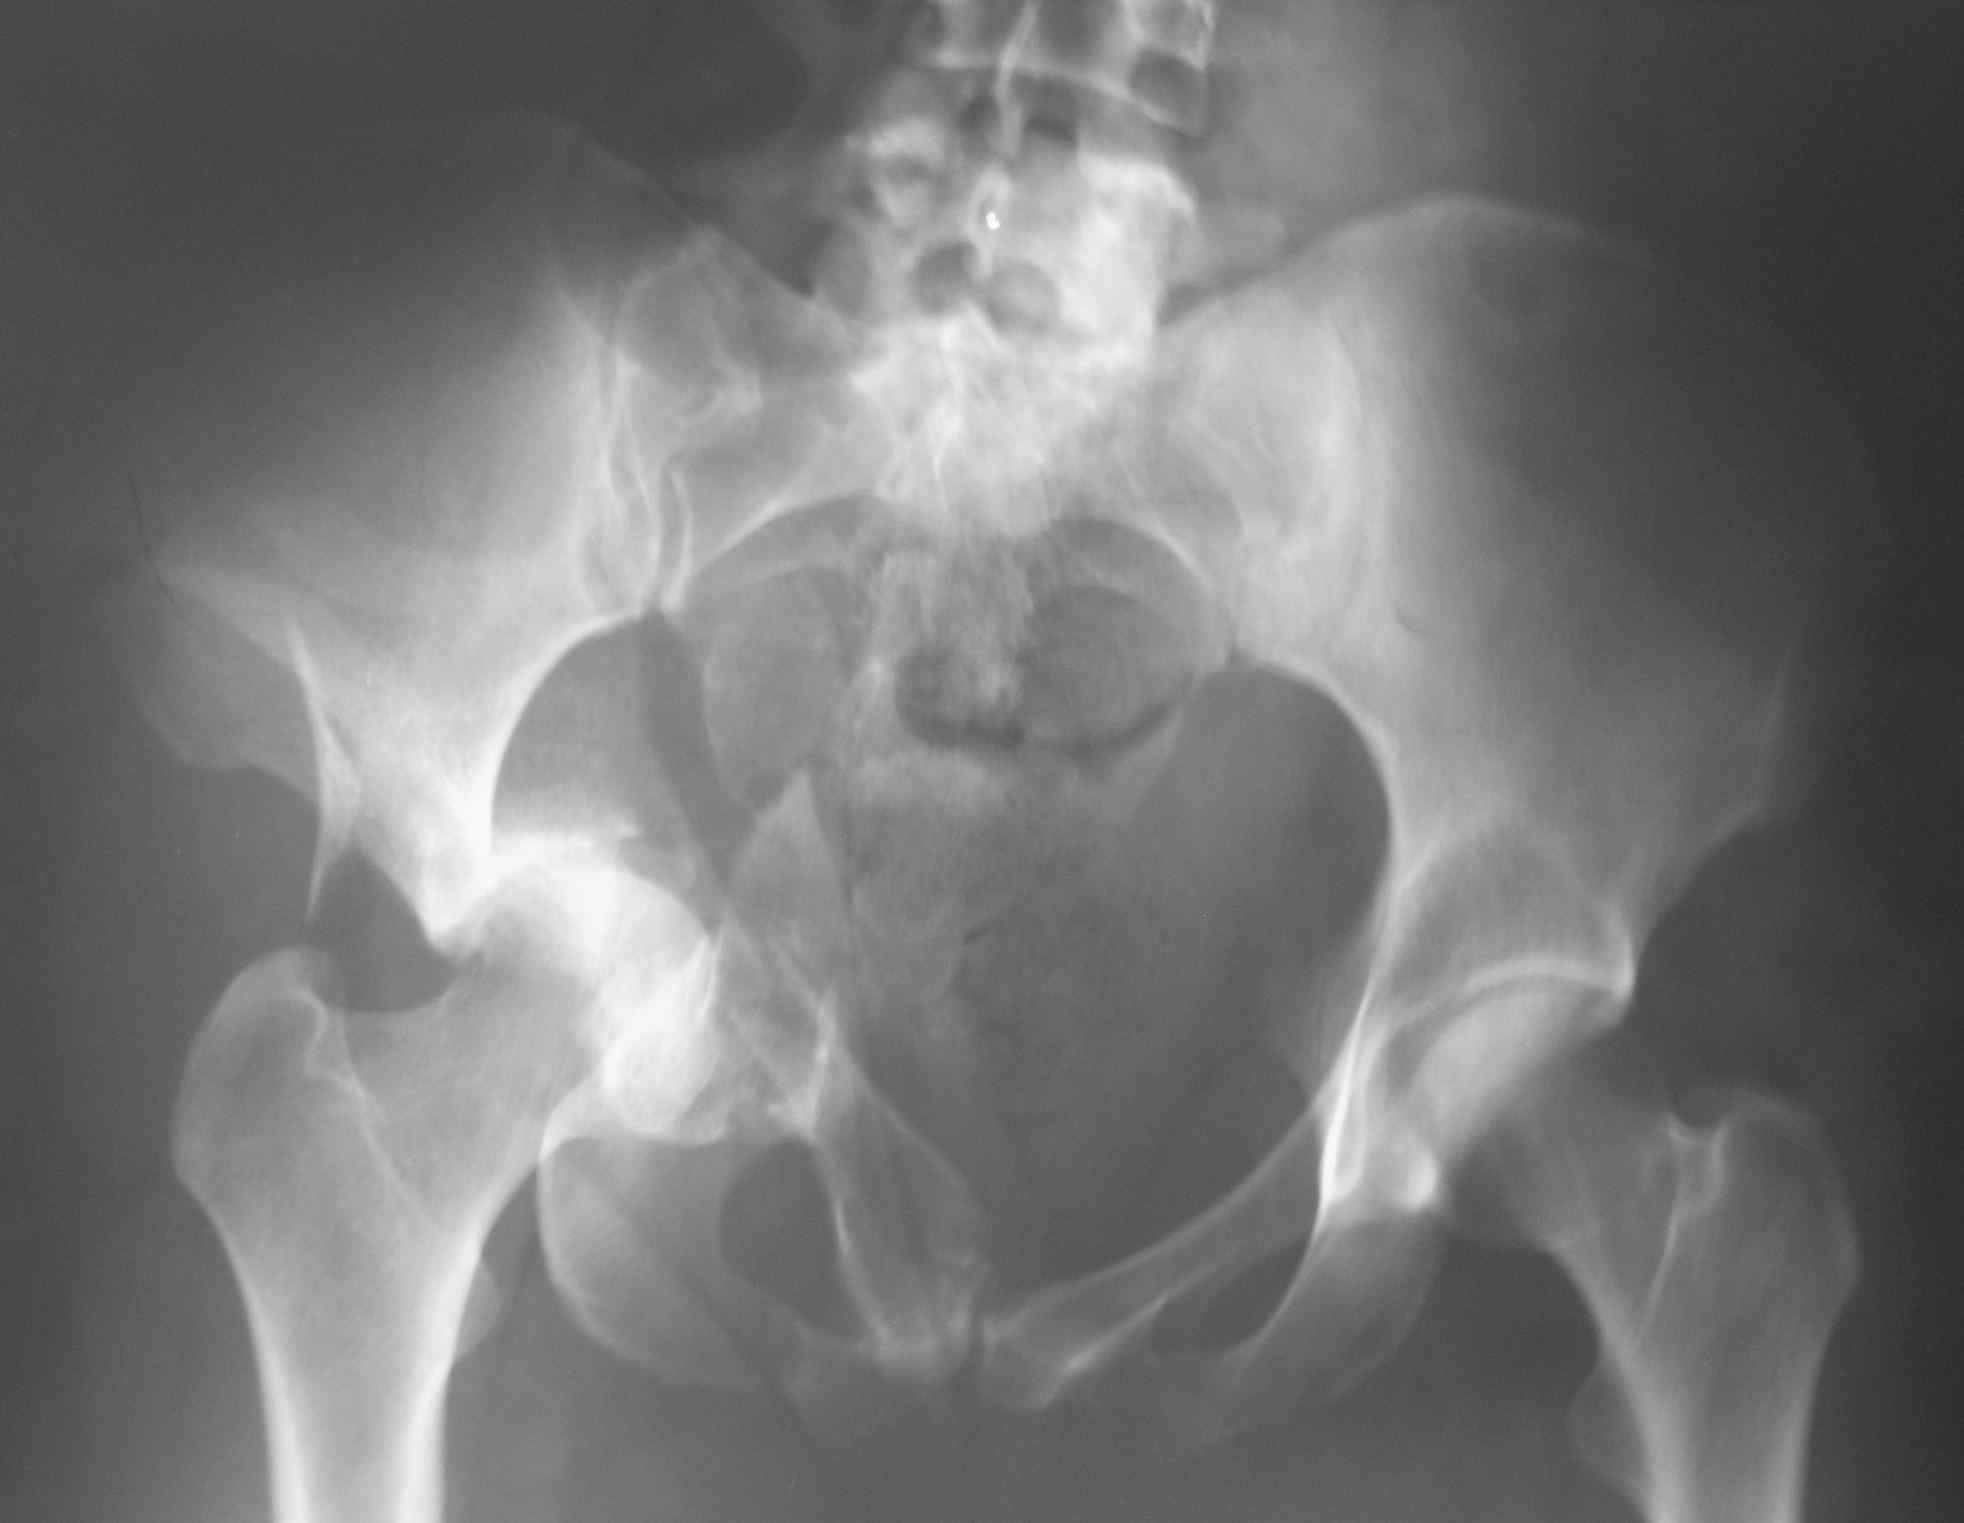

Re: Перелом костей таза

Большое спасибо за содержательные советы. Вот снимок при поступлении.